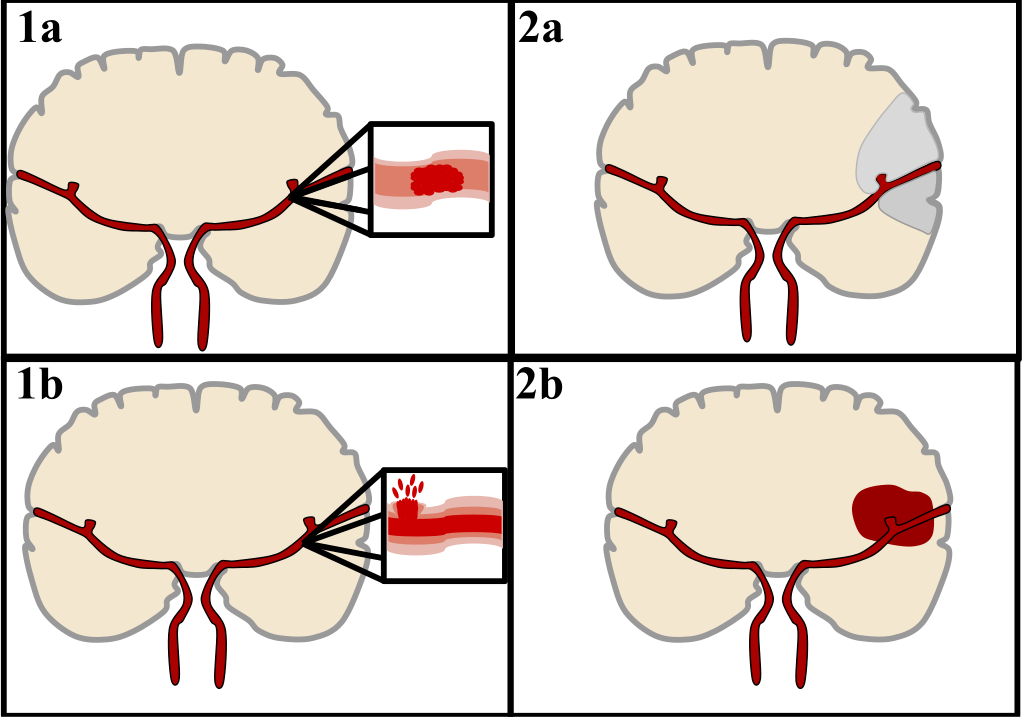

Een beroerte treedt op wanneer de bloedtoevoer naar de hersenen wordt onderbroken, waardoor hersencellen afsterven. Dit kan leiden tot verschillende fysieke en cognitieve beperkingen. Er zijn twee hoofdtypen beroertes:

- Ischemische beroerte– Veroorzaakt door een bloedprop die de bloedstroom naar de hersenen blokkeert of vernauwt. Dit type komt in ongeveer 87% van de gevallen voor.

- Hemorragische beroerte– Ontstaat door een bloeding in of rond de hersenen, wat druk veroorzaakt en hersenweefsel beschadigt.